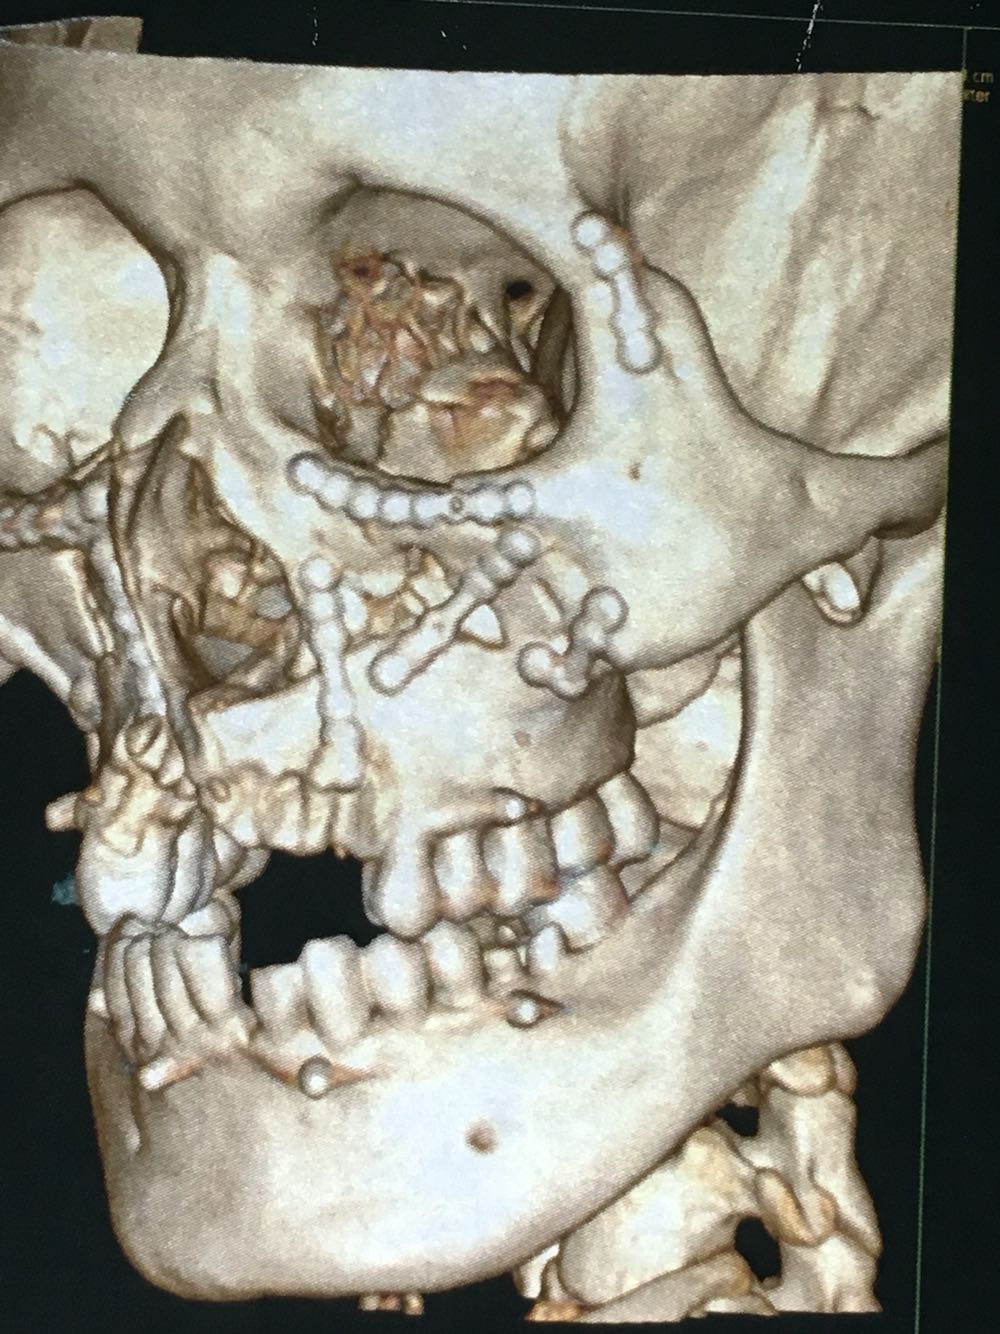

主诉:上颌骨骨折及锁骨骨折术后1年要求拆除内固定装置

治疗:全麻下双侧上颌骨骨折术后留置钛板取出及锁骨骨折术后钢板取出

讨论:颌骨内固定材料现在基本都主张手术取出,这个病人锁骨内固定材料由口腔科医生手术的,有超范围行医行为,最好由骨科完成。